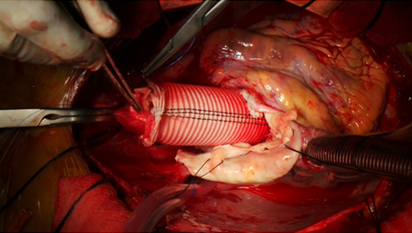

Surgery involves replacing the weakened section of the vessel with an artificial tube, called a graft. This means that surgeons will have to open either the stomach area (for abdominal aneurysms) or the chest (for thoracic aneurysms).

The bulging section of the aorta is cut out (excised). The surgeon will then replace the missing piece with a fabric tube called a graft. The clamps are then removed slowly to allow blood to flow through the vessel again.

Surgery of Replacing The Ascending Aorta using Artificial Valved Conduit

Replacement of Diseased Aorta with a Artificial Graft